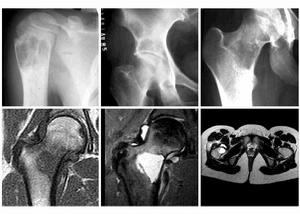

單房性骨囊腫診斷本症的診斷主要靠X線檢查和病理活檢。X線照片上顯示骨幹部中心性大透亮區有助於診斷。局部骨皮質變薄,體積略有膨脹。

X線檢查:囊腫一般位於長管狀骨的一端,局部骨幹的骨皮質略向外膨脹囊與骺板之間尚間隔有一小段松質骨。囊腫距骺板的遠近依病變發生時間的久暫和範圍而定。偶見囊腫穿透骺板進入骨骺如發生骨折,囊腫與骺板之間的松質骨可發生變形,但骨折多無移位